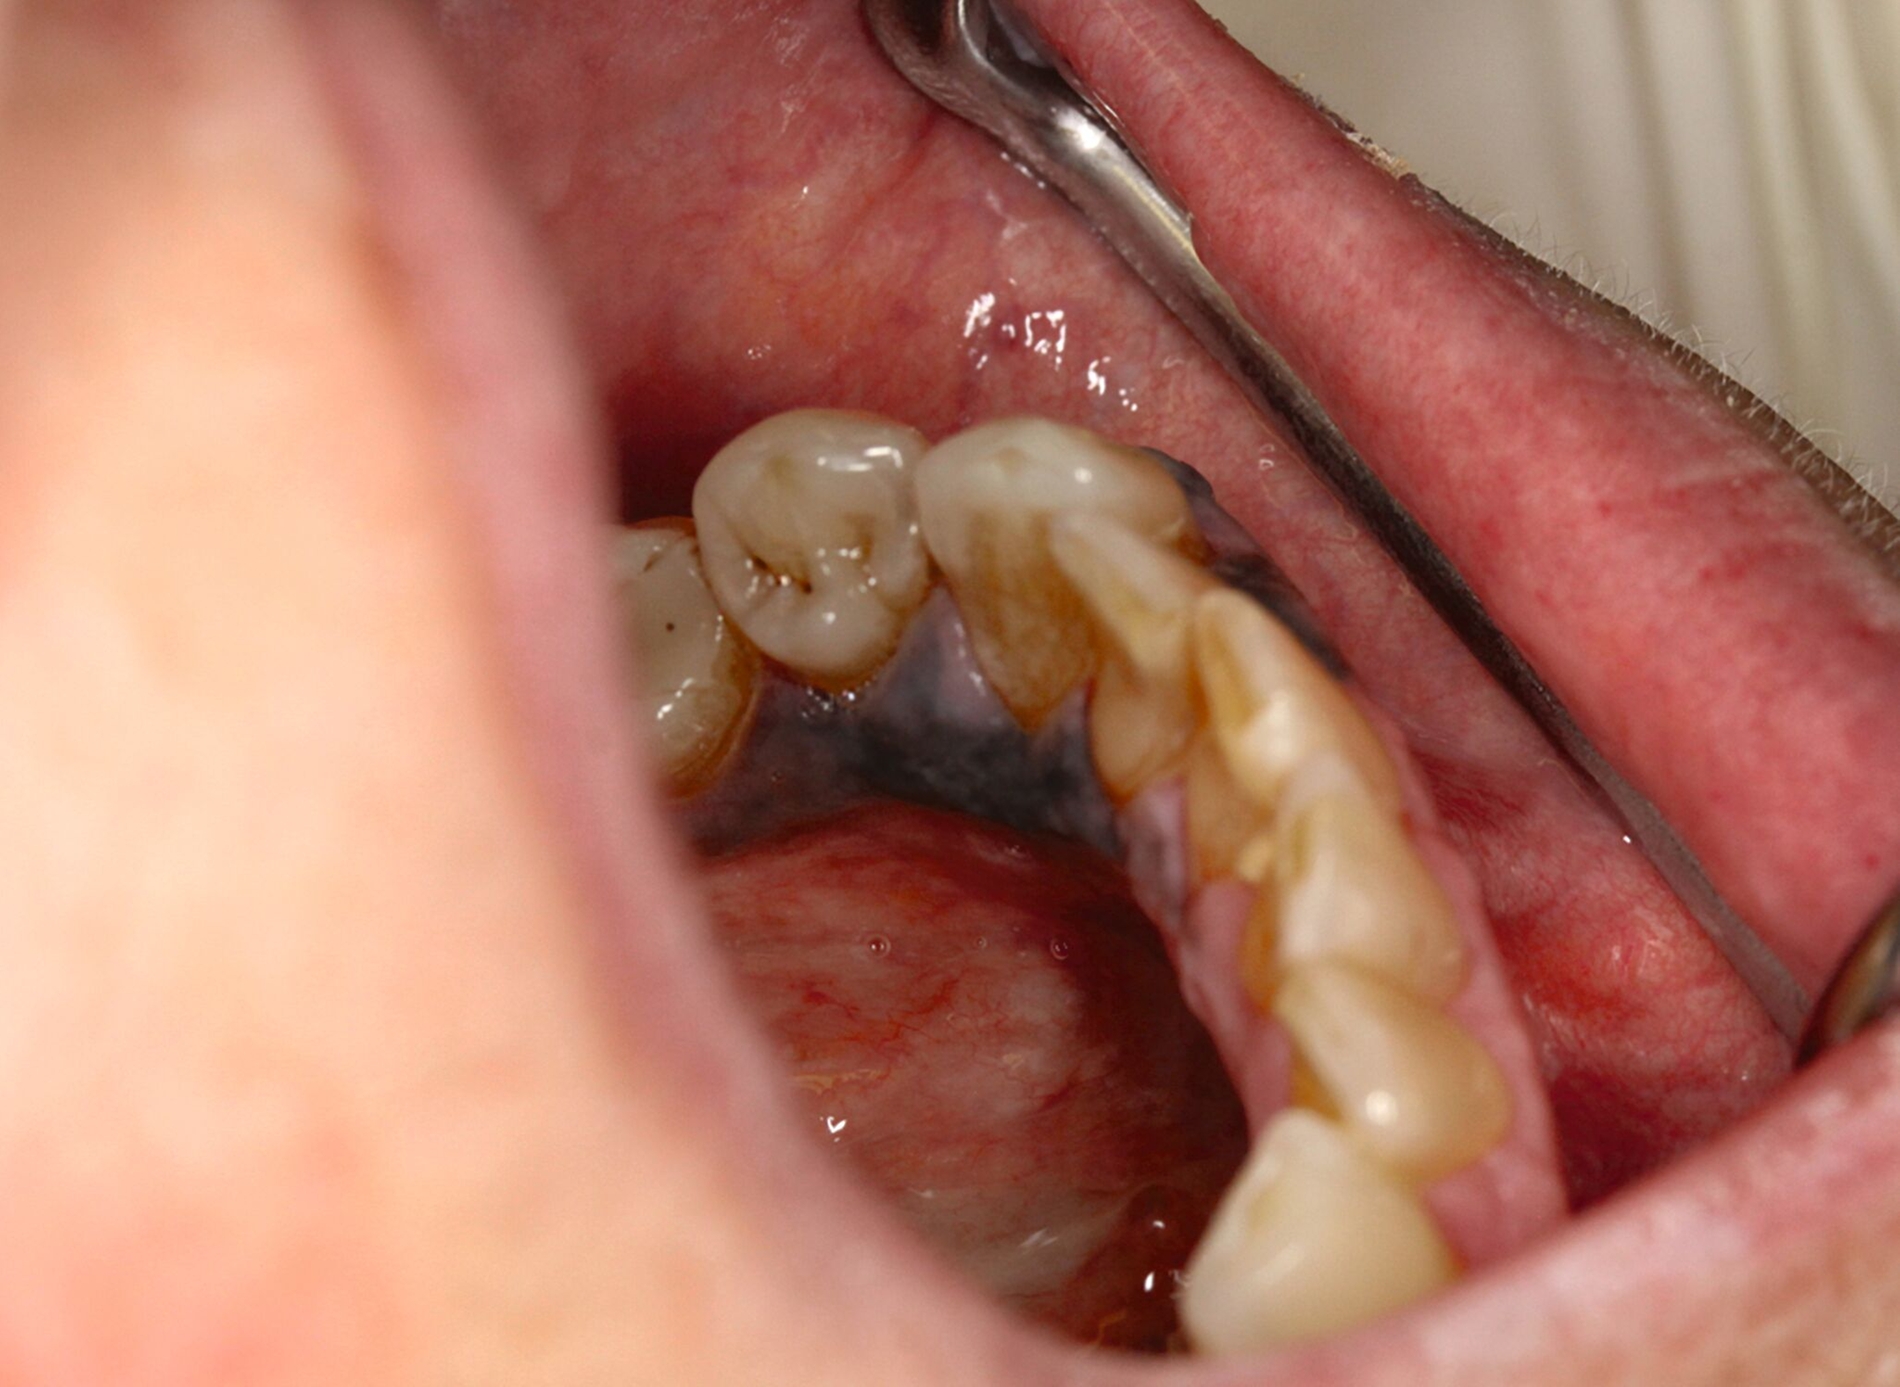

Eine im Januar 2024 alio loco durchgeführte Probenentnahme ergab eine resorptive Entzündung mit Pigmenteinlagerungen. Die Patientin berichtet, dass die Schleimhautveränderung etwa vier Wochen vor der Vorstellung bei uns begonnen habe zu wuchern. Klinisch zeigte sich eine 10 mm x 7 mm messende, exophytisch wachsende, schwarz pigmentierte Raumforderung (Abbildungen 1 und 2). Durch eine Probenentnahme in domo konnte histopathologisch ein malignes Melanom gesichert werden.